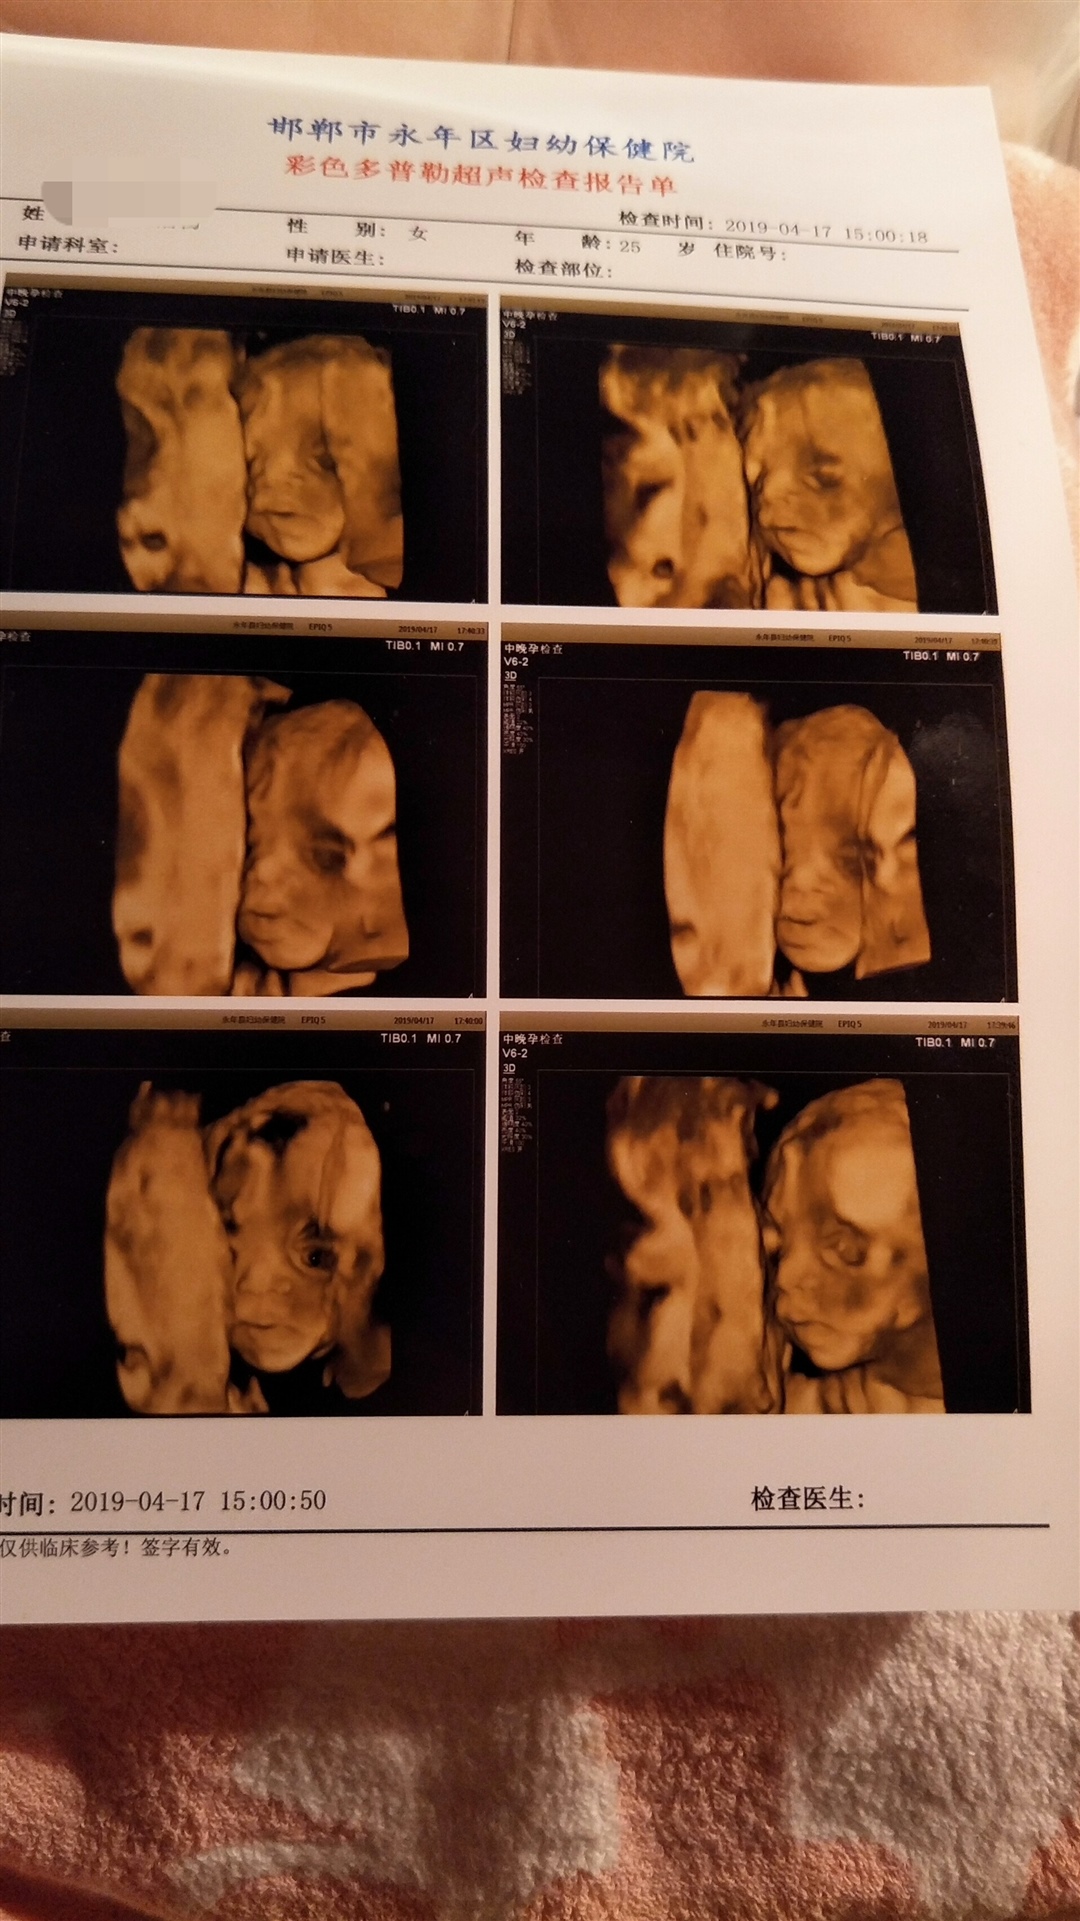

孕28周+2天

肚子里还会睁眼睛的?

孕24周+6天

看着像女孩